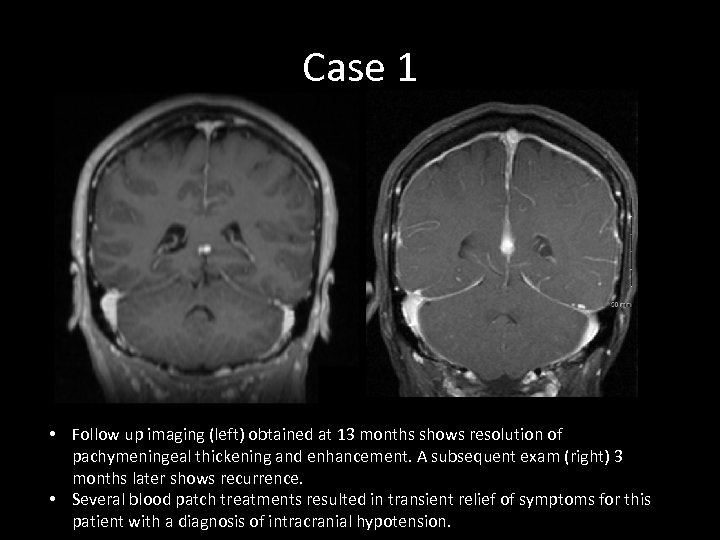

Case 1 • Follow up imaging (left) obtained at 13 months shows resolution of pachymeningeal thickening and enhancement. A subsequent exam (right) 3 months later shows recurrence. • Several blood patch treatments resulted in transient relief of symptoms for this patient with a diagnosis of intracranial hypotension.

Case 1 • Follow up imaging (left) obtained at 13 months shows resolution of pachymeningeal thickening and enhancement. A subsequent exam (right) 3 months later shows recurrence. • Several blood patch treatments resulted in transient relief of symptoms for this patient with a diagnosis of intracranial hypotension.